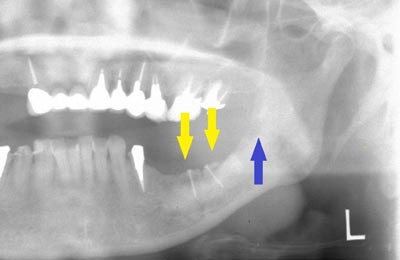

インプラントを埋入するためには、骨を増やさなければならず、患者様ご自身の骨を移植する、自家骨移植術を行なうこととしました。写真、青色の矢印で示す、智歯周辺の骨を採取し、黄色の矢印の部位に骨片を移植、チタン製の小さなスクリューで骨片を固定するという手術を行いました。細く、白く映っているのが骨を固定したミニスクリューです。

インプラントを埋入するためには、骨を増やさなければならず、患者様ご自身の骨を移植する、自家骨移植術を行なうこととしました。写真、青色の矢印で示す、智歯周辺の骨を採取し、黄色の矢印の部位に骨片を移植、チタン製の小さなスクリューで骨片を固定するという手術を行いました。細く、白く映っているのが骨を固定したミニスクリューです。